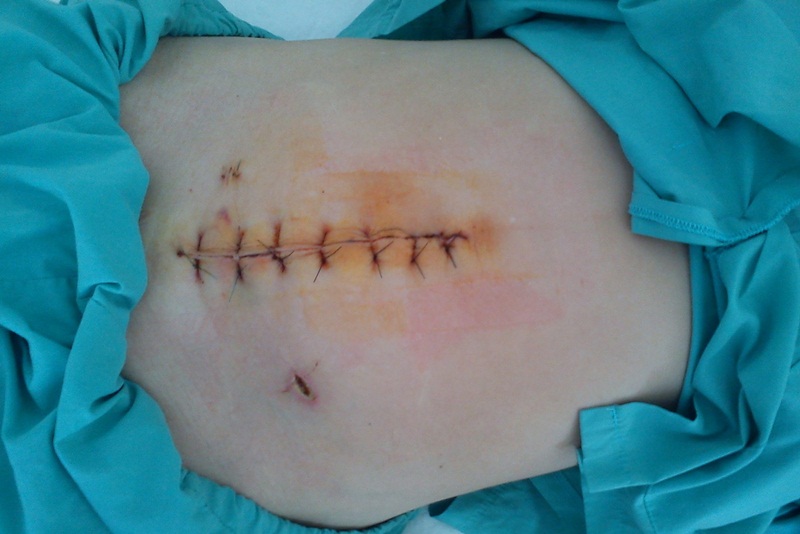

Chị em sinh mổ thường sẽ phải mất 3 - 4 ngày nằm lại bệnh viện để các bác sĩ sản khoa theo dõi cũng như cần 6 tuần nghỉ ngơi tại nhà để cơ thể hồi phục hoàn toàn. Sau thời gian này, chị em cần đi tái khám và bác sĩ sẽ có thể tiến hành siêu âm vết mổ sau sinh để đánh giá tổng quan vết mổ cùng quá trình phục hồi của sản phụ.

Siêu âm vết mổ sau sinh là bước quan trọng trong quá trình hồi phục của mẹ sau sinh mổ. Sau ca phẫu thuật, các bà mẹ thường nằm viện 3 - 4 ngày để theo dõi, sau đó là 6 tuần nghỉ ngơi tại nhà. Thời gian phục hồi có thể khác nhau tùy theo từng người vì mức độ chịu đau của từng cá nhân và tình trạng sức khỏe tổng thể là khác nhau.

Vào khoảng tuần thứ 6 sau khi sinh mổ, các bà mẹ nên đi khám sức khỏe để bác sĩ kiểm tra khả năng lành vết mổ hoàn toàn. Trong lần tái khám này, bác sĩ có thể đề nghị siêu âm vết mổ sau sinh để đo chính xác độ dày tại vị trí vết mổ, mục đích là để đảm bảo quá trình phục hồi đang diễn ra đúng hướng và không có biến chứng.

Tóm lại, siêu âm kiểm tra vết mổ sau sinh là bước quan trọng để bác sĩ chuyên khoa có thể đánh giá toàn diện quá trình phục hồi cũng như kịp thời phát hiện biến chứng. Chị em sau sinh mổ khoảng 6 tuần nên đi tái khám theo hẹn để được kiểm tra sức khỏe tổng thể. Ngoài ra chị em cũng cần phải tuân thủ đúng các dặn dò của bác sĩ để góp phần bảo vệ sức khỏe, tránh những biến chứng nguy hiểm có thể xảy ra.